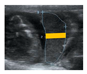

| Transversal area of placenta (PA) | Region observed in a transversal visualization of placenta excluding decidua | mm (perimeter), mm2 (area) | ![]() |

| Placental length (PL) | Longitudinal segment in a transversal visualization of placenta | mm | ![]() |

| Placental thickness (PT) | Transversal segment in a transversal visualization of placenta | mm | ![]() |